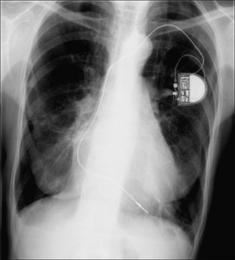

image

Figure 12.7 Optimal electrode position. Single chamber pacemaker. The ventricular lead has its tip situated at the apex of the right ventricle. (Retouched.)

Figure 12.8 Optimal electrode positions. Dual chamber pacemaker. The atrial lead has its tip in the right atrium; the ventricular lead has its tip at the apex of the right ventricle. (Retouched.)